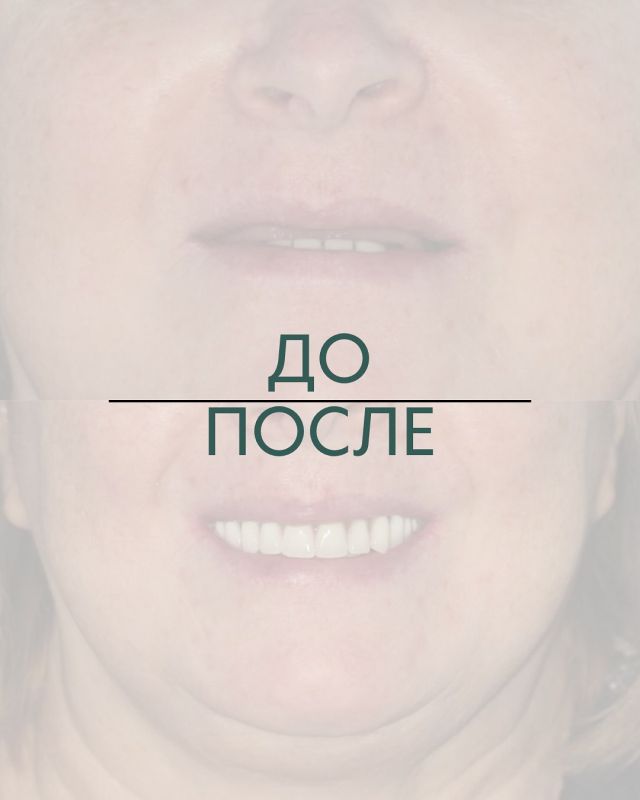

Клинические случаиИмплантация All-on-4 Имплантация All-on-6 Имплантация All-on-8 Синус-лифтинг